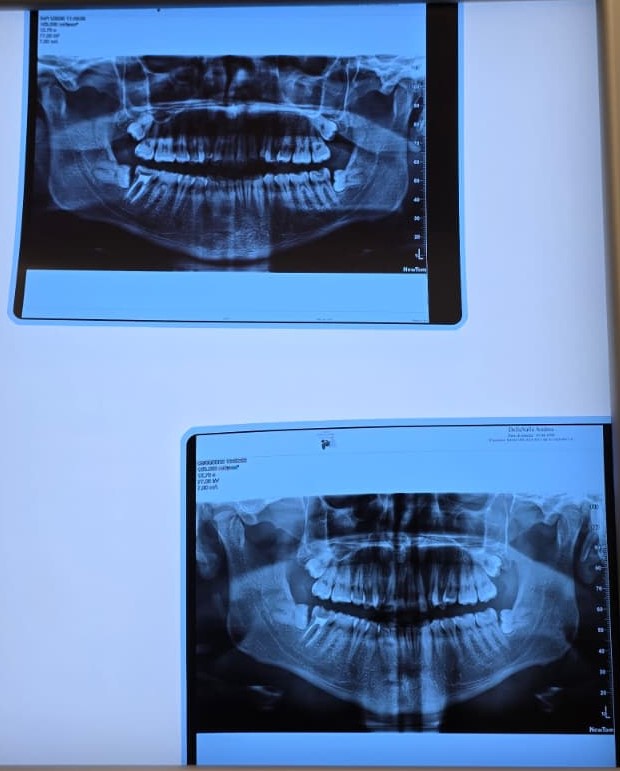

Eppure i superiori, come vedete dalla radiografia, sono particolarmente vicini al seno paranasale mascellare. Questa mattina l’estrazione del dente del giudizio superiore è stata difficile. Il medico ha avuto difficoltà nell’estrazione. Il dente è uscito, ma parte di una delle due radici è rimasta nel sito. Il medico l’ho visto particolarmente preoccupato, ma ha valutato che non si potesse estrarre senza il rischio di fare danni al seno e così ha deciso di chiudere la ferita e lasciare lì il pezzo rimasto.

Subito e velocemente, alla fine dell’operazione, ho fatto una TAC Cone Beam per valutare la radice e la posizione (la seconda in 4 mesi). Il medico mi ha fatto vedere e dice di aver valutato bene la scelta di aver lasciato il moncone della radice nel sito perché in una posizione difficile.